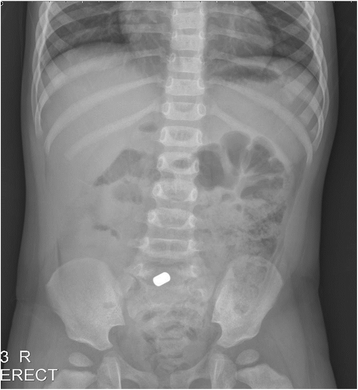

Background: Although foreign bodies (FBs) typically pass spontaneously and uneventfully through the digestive tract, a subset of such bodies may become trapped, eventually leading to significant injury. In particular, the ingestion of magnetic materials can cause serious morbidity due to proximate attraction through the intestinal wall.

Case presentation: We recently treated three pediatric patients who had ingested several magnetic foreign materials. None of these patients exhibited any clinical symptoms or signs suggestive of surgical abdomen. Moreover, it was difficult to determine a definite diagnosis and a treatment plan due to limitations in history taking and radiologic examination. After admission to the hospital, these patients underwent surgery for the following reasons: (1) failure to spontaneously pass ingested foreign materials; (2) sudden-onset abdominal pain and vomiting during hospitalization; and (3) gastric perforation incidentally discovered during gastroduodenoscopy. Subsequently, all patients were discharged without complications; however, their conditions might have been fatal without surgery at an appropriate time.

Conclusions: As the clear identification about the number and characteristics of ingested magnets via radiographic examination or patient history appears to be difficult in pediatric patients, close inpatient observation would be required in any case of undetermined metallic FB ingestion. Patients who are confirmed to have ingested multiple magnets should be regarded as conditional surgical patients, although their clinical conditions are stable.